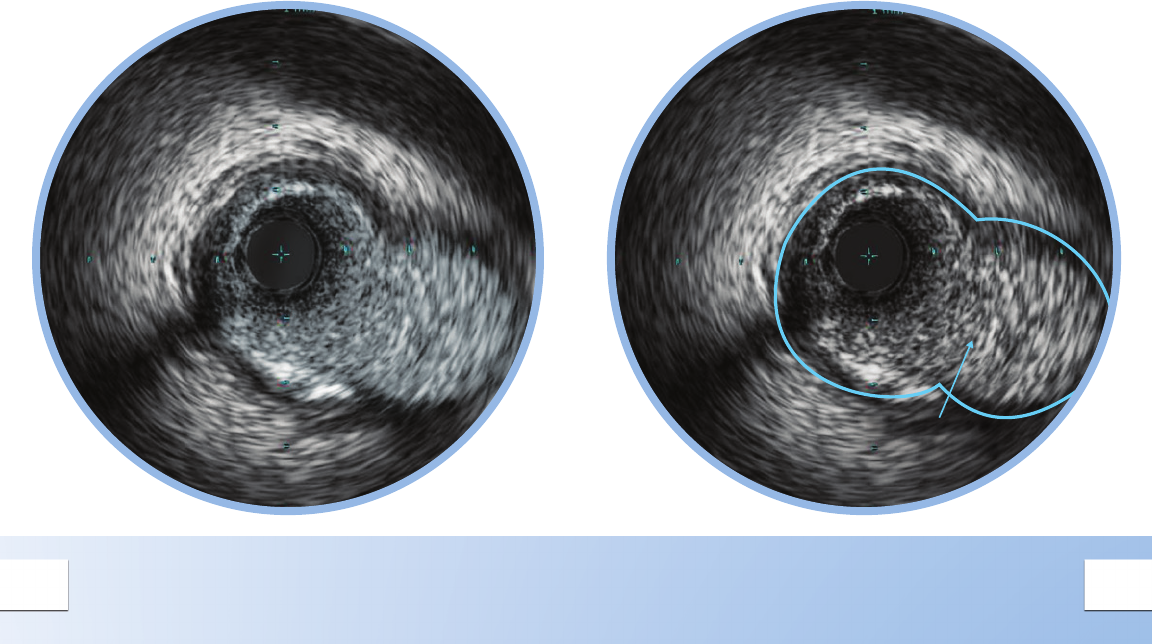

VEIN GRAFT DISSECTION

A dissection, or tear in the vessel wall can be

seen as a ap with blood ow behind it.

Only the intimal layer is dissected.

When detecting a dissection, the catheter may be

ushed with contrast to reduce the blood speckle.